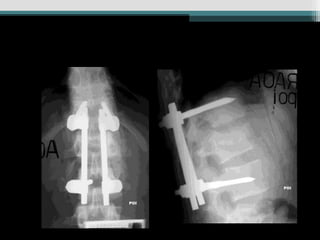

Caso 4 (19anos, auto, Fk e)